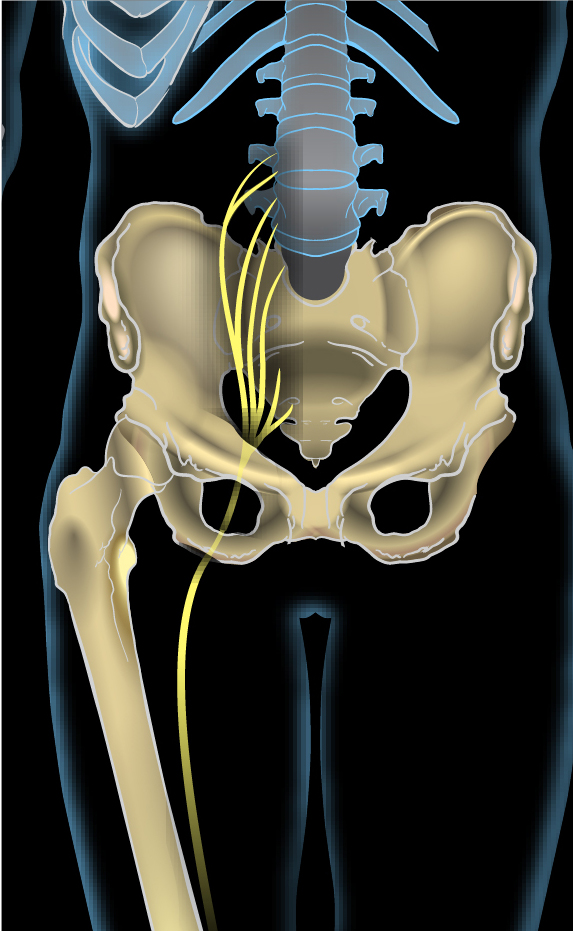

عرق النسا للرجال هو حالة صحية ناتجة عن ضغط أو تهيّج في العصب الوركي، وهو أطول وأكبر عصب في الجسم، يمتد من أسفل الظهر مرورًا بالأرداف والفخذين وصولًا إلى أسفل الساقين. وعندما يتعرض هذا العصب للضغط، يبدأ الألم في أسفل الظهر ويشعّ نزولًا إلى الساق، وقد يكون الألم مصحوبًا بوخز أو تنميل أو ضعف عضلي في الرجل المصابة.

يحدث عرق النسا للرجال غالبًا نتيجة انزلاق غضروفي في الفقرات القطنية، وهو ما يؤدي إلى ضغط مباشر على العصب الوركي. كما يمكن أن تنجم الإصابة عن الجلوس لفترات طويلة، أو رفع أشياء ثقيلة بطريقة خاطئة، أو بسبب تضيّق العمود الفقري مع التقدم في العمر. وتُعد المهن التي تتطلب مجهودًا بدنيًا أو قيادة لفترات طويلة من العوامل المساهمة أيضًا في تطور عرق النسا للرجال.